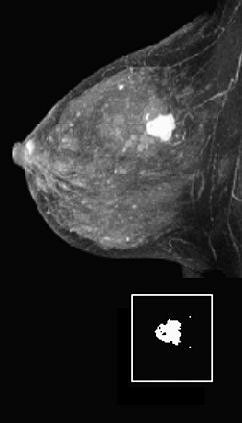

|  |

| Fifty-year-old woman with invasive ductal carcinoma, grade III, studied while undergoing neoadjuvant chemotherapy treatment. MRIL was performed using contrast-enhanced 3D fast gradient-recalled echo-pulse sequence. Patients presented with 22 cm3 (4.7-cm diameter) tumor. Significant reduction in MRI volume was evident after one cycle of chemotherapy (30% decrease) and by end of treatment (88% decrease). Patient had 2.2 cm of residual disease and one involved lymph node at surgery, and continues to be disease-free 20 months after surgery.  |